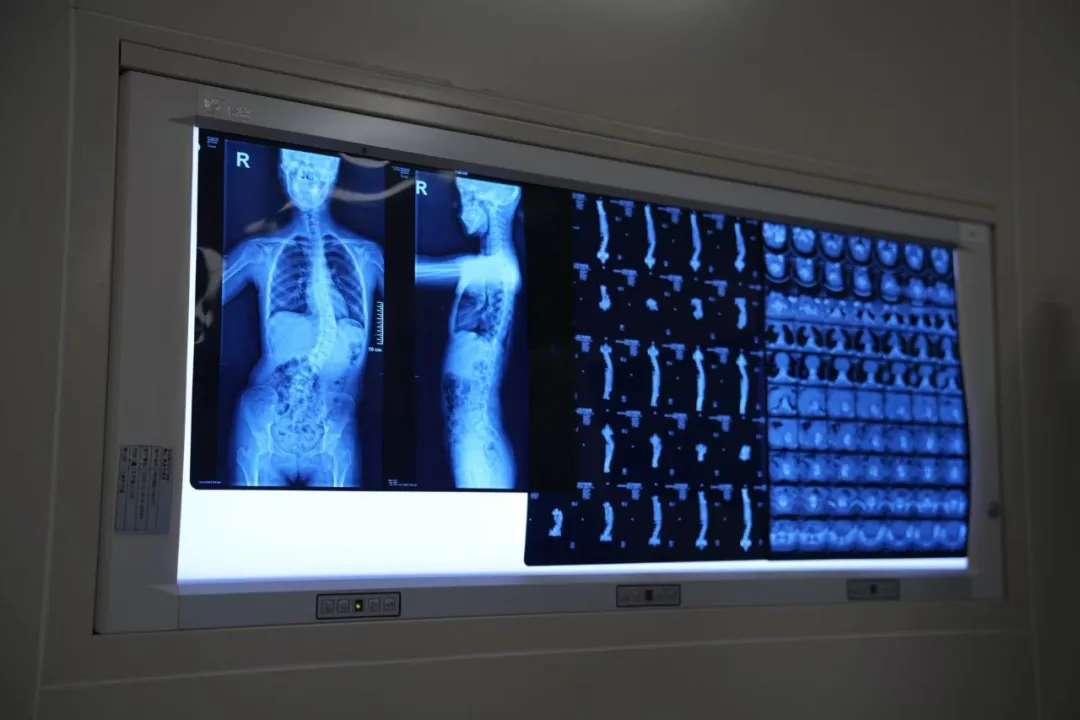

患者术前确诊脊柱侧弯8个月,脊柱呈S形畸形:胸椎左侧弯Cobb角约20°,腰椎右侧弯Cobb角约42°,伴有双肩不等高、胸廓不对称、肋骨突出等症状,已严重影响身心健康。